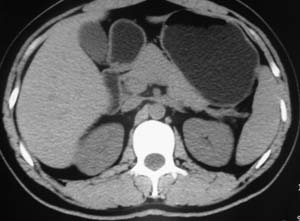

以下是引用子期在2010-3-19 20:47:00的发言:[br]血管畸形的ct增强应该有明显强化,本例并不相符合。本例双肾局部的略低密度影,累及肾盂,局部皮质明显变薄、内陷,增强扫描有轻度的强化,应考虑为炎性病变,患者为年轻男性,累及双肾的感染以结核较常见,可以没有明显的临床症状,尿中有时候也并不能查出什么;肾脓肿常有明显感染中毒症状,本例不符,另外一般的肾盂肾炎或肾小球肾炎通过小便就可确诊,其它还不能排除的是黄色肉芽肿性肾盂肾炎,然而单凭ct一般也很难鉴别。